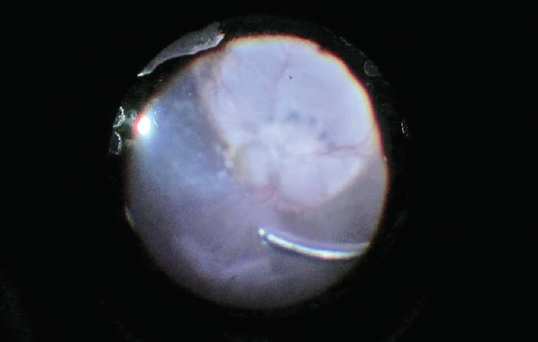

Here, we share the case report of an 8-year-old boy with bilateral coloboma of the optic nerve and the central inferior choroid, as well as the inferior iris as an associated finding (Figures 2 and 5). The patient first developed a macular detachment in the left eye, which quickly developed into a complete retinal detachment caused by fluid coming from the ODP and a suspected macular hole.

This case presented several challenges, including that the macular hole was in the area of the coloboma, that the coloboma was very deep, and that there was no retinal pigment epithelium over a large area.

We chose to perform lens-sparing complete PPV (Video). In the literature, similar cases have been managed with silicone oil as a final tamponade. As mentioned above, however, silicone oil can have a track to the CSF (and potentially the brain) in patients with ODP. Therefore, to offer a greater chance of retinal reattachment without the use of silicone oil, we decided to combine PPV with a macular buckle to support the atrophic macular area from the scleral side. This would serve to seal the pit with the buckling effect and to relieve traction and air tamponade.

We still wonder whether performing only the macular buckle and injecting a gas bubble could have solved the detachment. However, the difficulty in determining the cause of the total detachment convinced us to enter the eye. Only during surgery could we confirm that the cause of the patient’s pathology was a macular hole into the coloboma.

The surgery was performed in 2012. The retina remains attached, and the boy still retains a BCVA of 20/200 with extrafoveal fixation, the same vision he had before surgery.